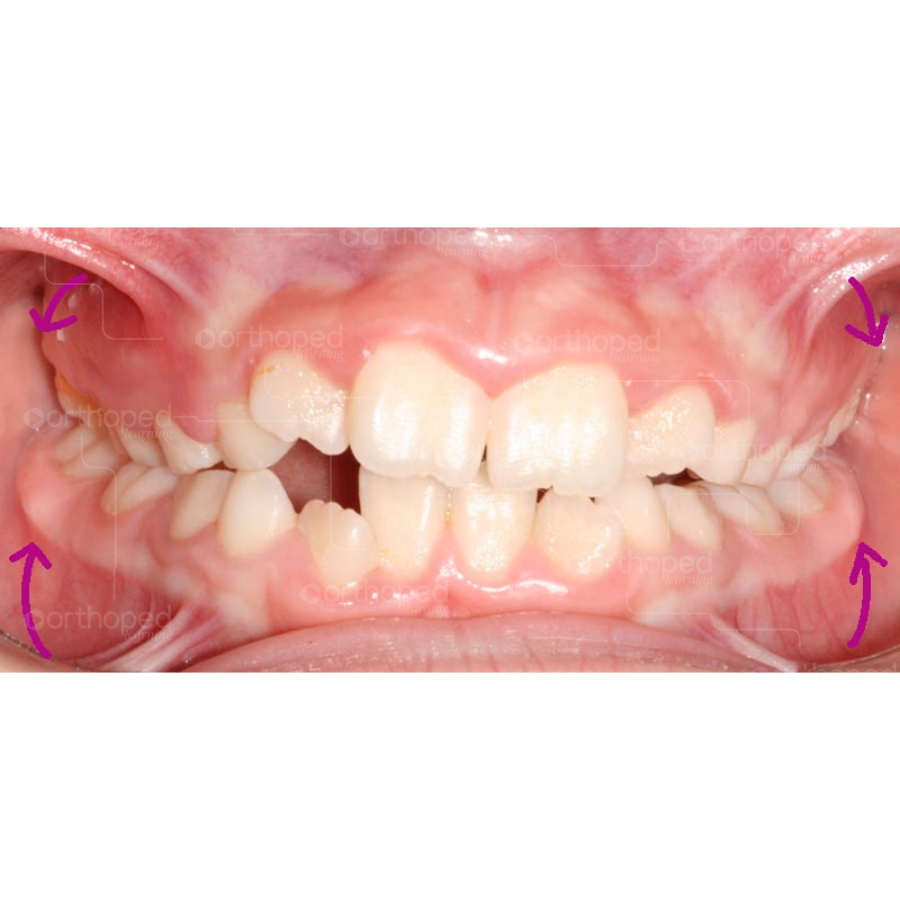

Observe abaixo a relação da borda Wala e a amplitude da maxila antes e após a expansão maxilar.

Antes da expansão maxilar.